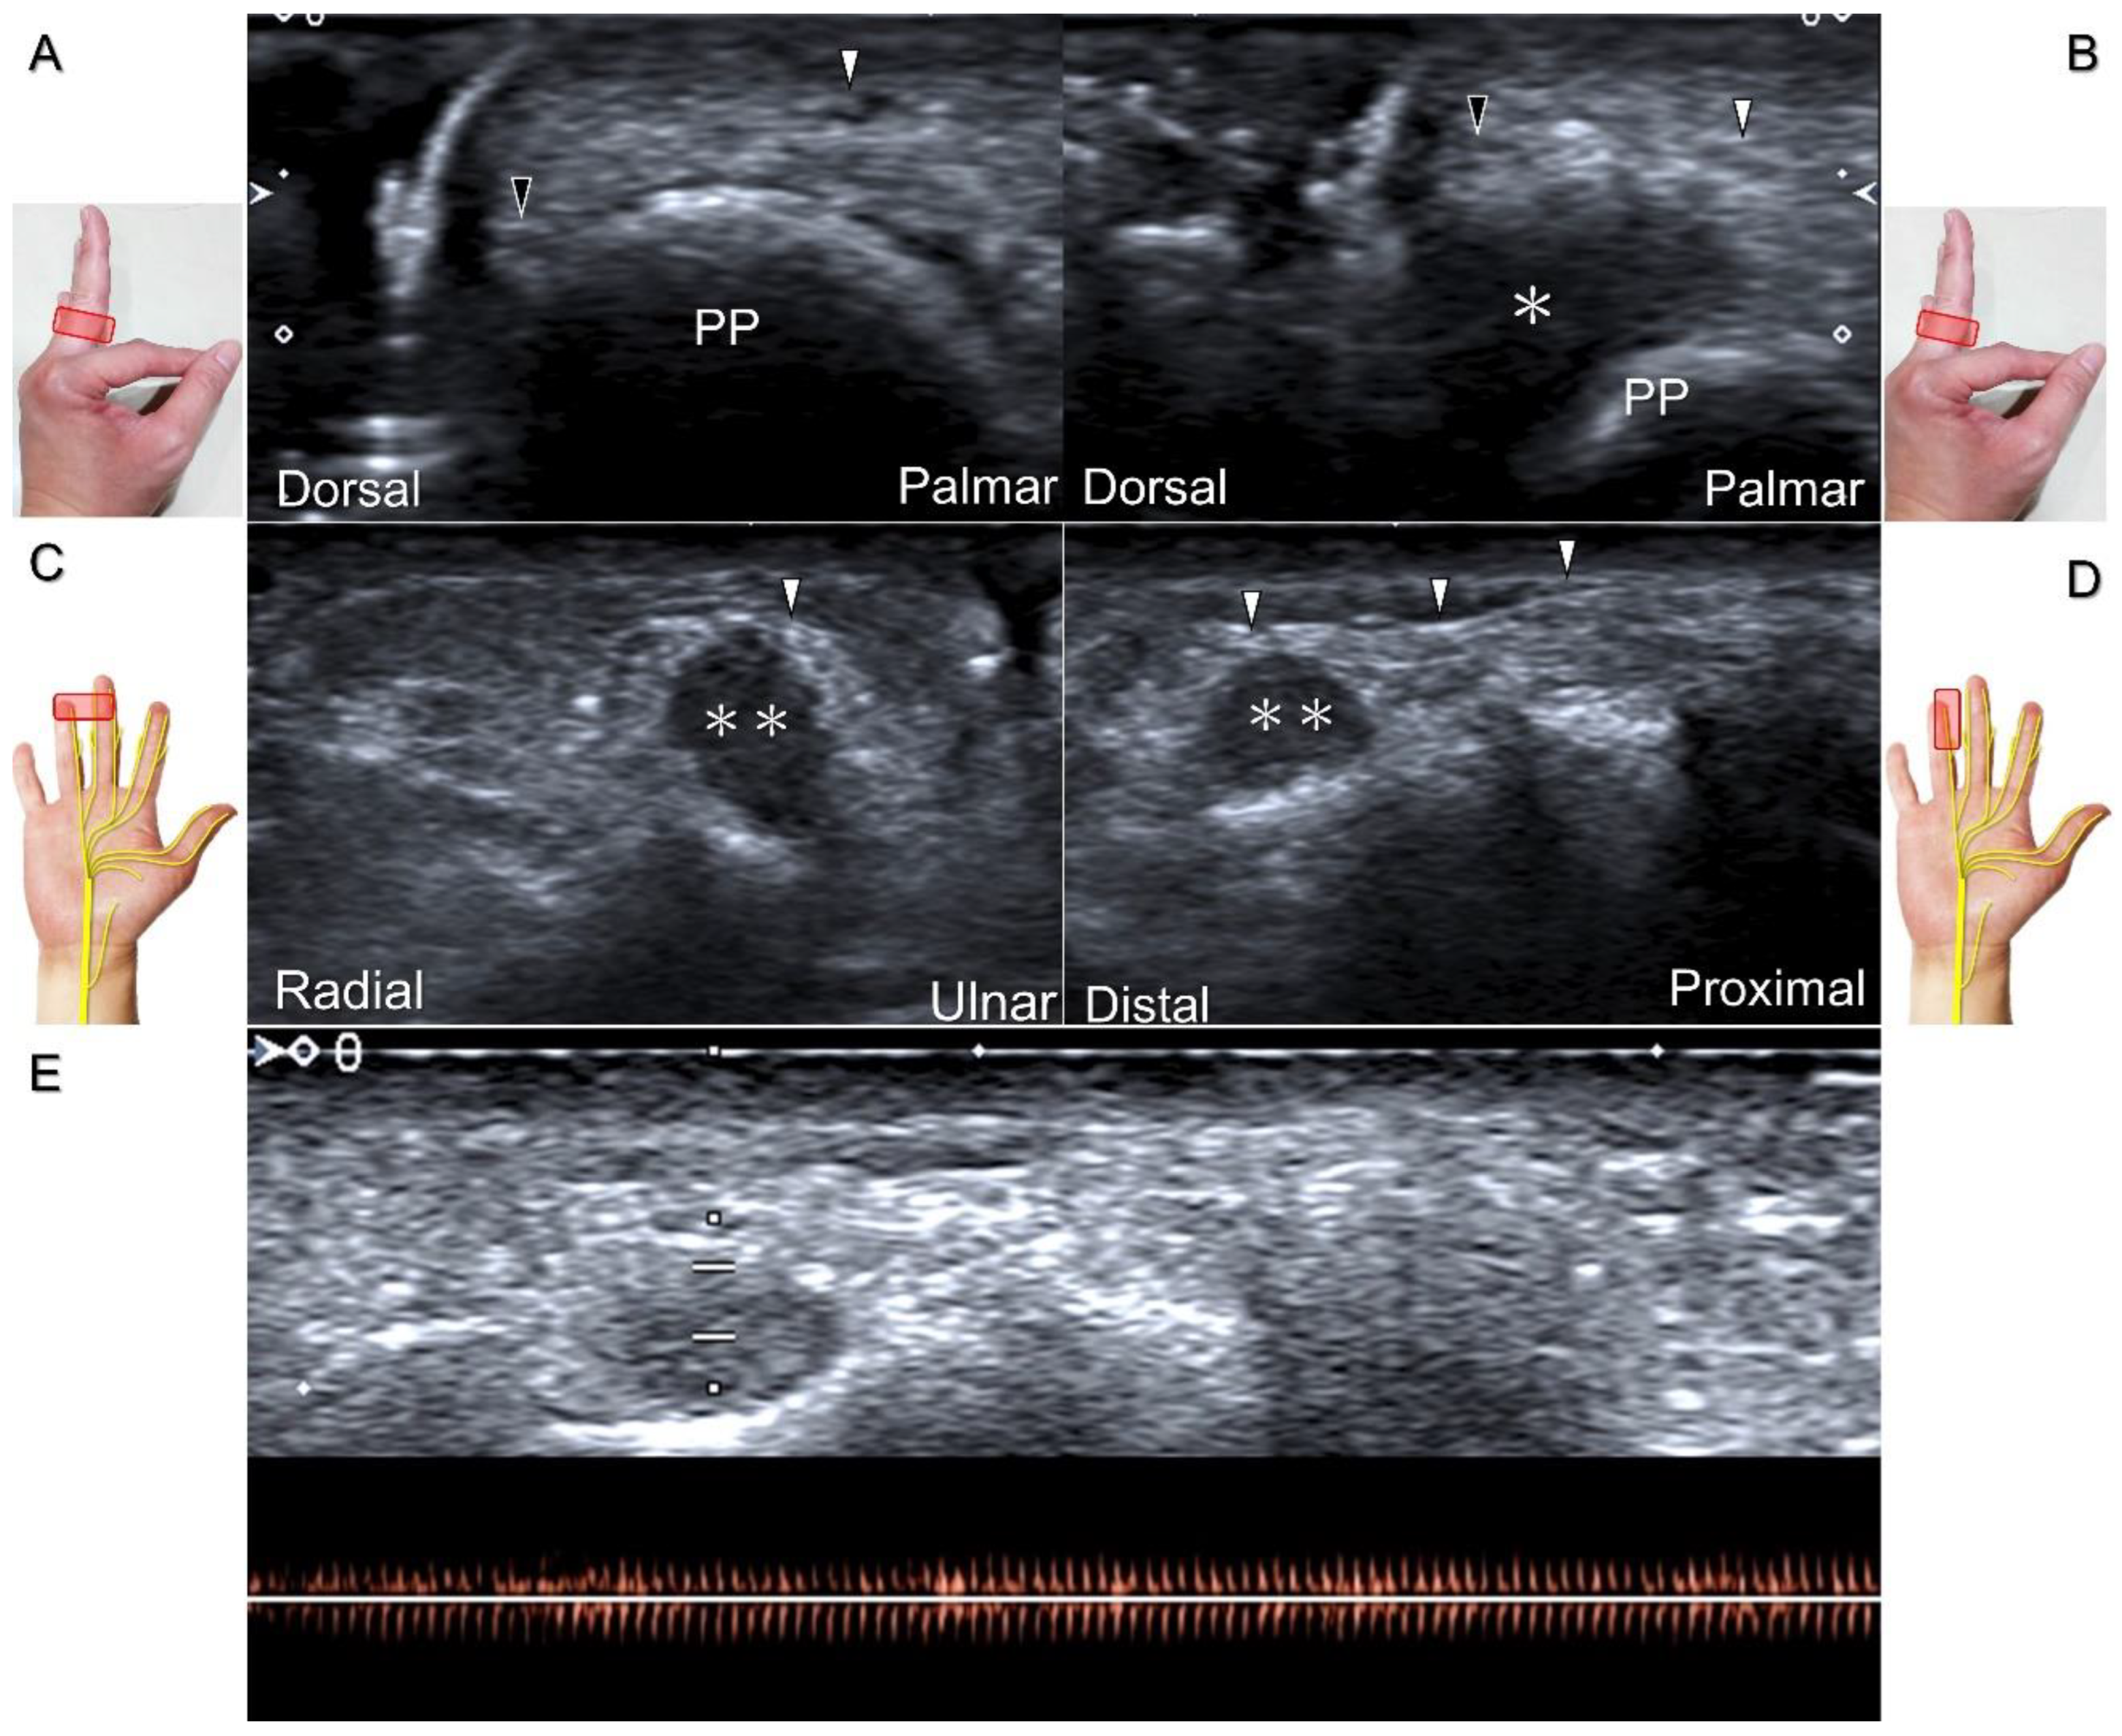

Clinical Implication

Direct injury of the palmar common digital nerve can occur due to various reasons such as trauma, contusion, or iatrogenically during tendon injection. Nerve entrapment caused by space-occupying lesions such as fractures, ganglia (Figure 29A–C), annular ligament tears (Figure 29D), tenosynovitis, foreign bodies, fibroma (Figure 30A,B), or hemangioma (Figure 30C–E) is also likely.

Figure 30. In comparison to the healthy side (A), short-axis imaging (B) shows irritation of both the palmar and dorsal proper digital nerves due to a fibroma (asterisk). Short-axis (C) and long-axis (D) imaging demonstrates irritation of the palmar proper digital nerve due to a hemangioma. Spectral Doppler mode (E) confirms the hemangioma. White arrowhead: palmar proper digital nerve; black arrowhead: dorsal proper digital nerve; double asterisk: hemangioma; PP: proximal phalanx.